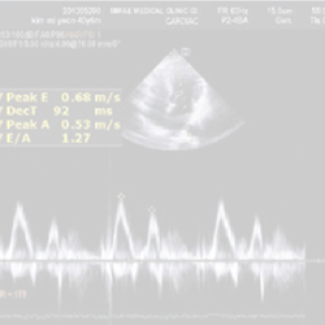

심장 초음파(경흉 심장 초음파)는 초음파를 이용하여 움직이는 심장의 해부학적 구조 이상, 심장기능, 심장 내 압력 등을 실시간으로 관찰합니다. 하지만 심혈관계 질환이 의심될 경우 심장 CT, 뇌 CT, 뇌 MRI+MRA 등을 추가로 실시할 수 있습니다.

• 심장 초음파

심장의 구조나 기능을 평가하는 검사로 심근경색증, 협심증, 심장판막증, 심근병증 등을 진단